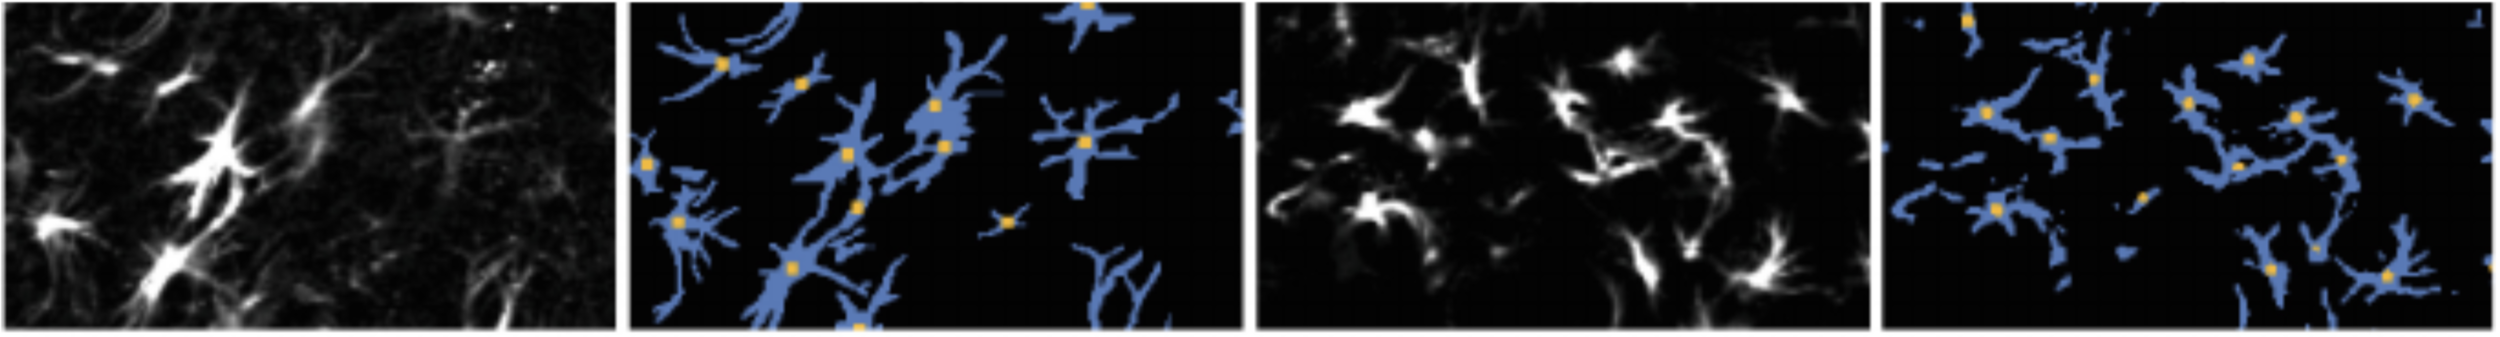

Data augmentation

Real

Ronneberger et al. (2015), Uzunova et al. (2017)

Deformed

Generated